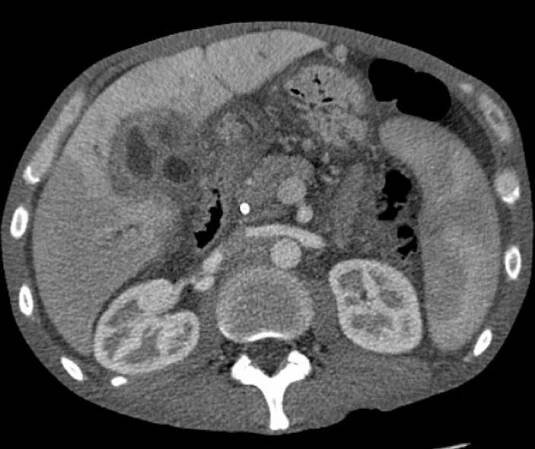

Hepatocelulární karcinom (HCC) je nejčastější primární maligní nádor jater. Celosvětově je hepatocelulární karcinom pátým nejčastějším nádorem u mužů a osmým u žen. K rozvoji tohoto karcinomu dochází nejčastěji u pacientů s chronickým jaterním onemocněním, obvykle v terénu cirhózy různé etiologie…

Hepatocelulární karcinom (HCC) je nejčastějším primárním maligním nádorovým onemocněním jater. Podle údajů systému Globocan bylo na celém světě v roce 2018 registrováno 841 080 případů HCC, ve stejném roce a podle stejného zdroje bylo…